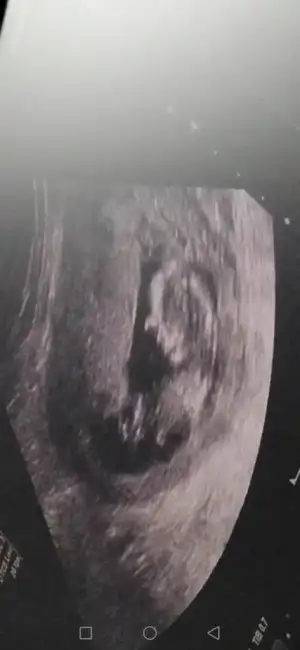

Net değilKizlar kim yorumluyor burda nub teorisini..Ben 18.hafta icindeyim gerci ama hala ogrenemedim cinsiyetini beninkinede bakarmisiniz bu da eksik kalmasınburda 12+2 gunluk videoda cektim goruntuyu tam bu bolge sanirim baktiginiz

Nubu ne dik nede paralel tam karşıya bakıyor nubu böyle usgler yanıtıyor beni başka usg varmı nubu erkek desem erkek gib tam dik değilBen de yorum istiyoruuum12+2 burdaEki Görüntüle 2633538

net degilmi kocaman gözüküyor ekranda cıkınti anlamadimNet değil

O nub değilnet degilmi kocaman gözüküyor ekranda cıkınti anlamadim![]()